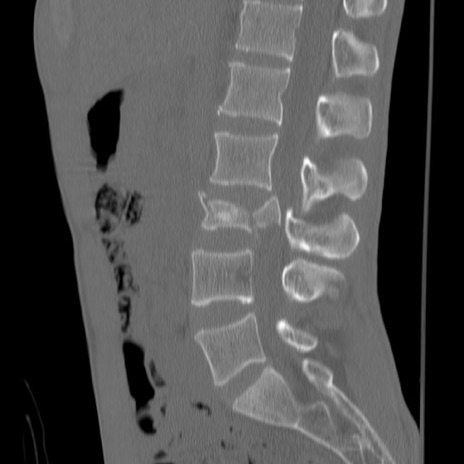

症例3 腰椎CT(矢状断像)

腰椎CT